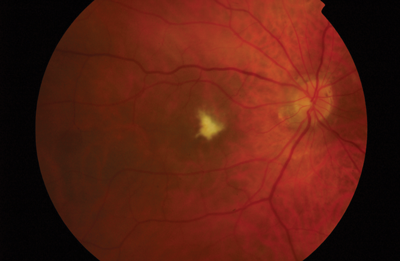

On a following visit to the macula clinic, patient underwent peripheral retinal examination which confirmed the presence of a shallow inferior retinal detachment in association with small infero-temporal U-tear. Interestingly, following the ranibizumab injections, macula appeared to re-attach. Patient was counselled about the findings and subsequently underwent left 23G pars plana vitrectomy, C2F6 gas and endolaser for repair of the retinal detachment. Following reattachment surgery the left eye did not show any signs of dry AMD (Figure 2). Retinal detachment (RD) is a recognised rare complication of intravitreal injections with an incidence of 0.013% [2]. However, the presence of a small post-oral u-tear typically seen in pseudophakic retinal detachments and the presence of inferior subretinal fluid bisecting the macula, were in keeping with a rhegmatogenous pathogenesis on presentation.

Figure 2 (top and above): Colour fundus photographs of both eyes following left retinal detachment repair.

Left macula shows no evidence of age-related macular degeneration.